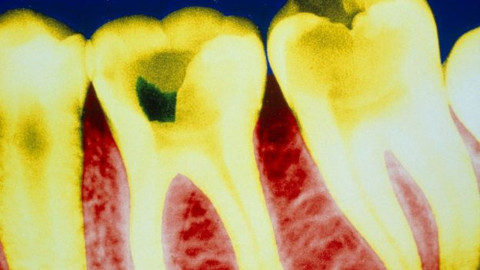

Aspirinin ağrı kesici özelliği ve kan sulandırmadaki faydaları biliniyordu. Yeni faydası ise bilim dünyasını heyecanlandırdı. Çünkü araştırmalara göre aspirin çürüyen dişin iyileşmesine ve hatta dişin kendini tamir etmesine yardım ediyor.

Kuzey İrlanda'daki araştırmacılar, aspirinin diş çürümesini geri çevirip dişte oluşan kaviteleri tedavi edebileceğini ortaya koydu.

En yaygın diş hastalığı olan çürük, diş sinirinin iltihaplanmasına ve diş ağrısına neden oluyor.

Kendi hücrelerini yenileyebilme kabiliyetleri sınırlı olan dişlerin çürümesi halinde dolgu teknolojisi kullanılıyor. Ancak bu dolguların insan hayatı boyunca birkaç kez değiştirilmesi gerekiyor. Queen's Üniversitesi Diş Hekimliği ve Biyomedikal Bilimler Fakültesi öğretim görevlisi Profesör Ikhlas El Karim, aspirinin diş kökü hücrelerini onarmasıyla dolgulara olan ihtiyacın ortadan kaldıracağına dair çalışmalar yapıyor.